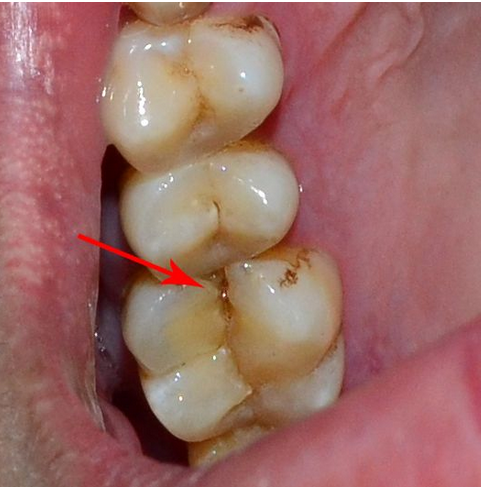

这很可能是“牙隐裂”在作怪!

牙隐裂:指牙冠表面的非生理性细小裂纹,常不易被发现。牙隐裂的裂纹常深入到牙本质结构,是牙齿敏感及牙痛的原因之一。牙齿上的这个小小裂纹如果没及时发现并治疗,那么它最终可能导致牙齿折裂,甚至最终造成失牙。

牙隐裂发生于上颌磨牙最多,下颌磨牙和上颌前磨牙次之;第一磨牙明显多于第二磨牙,近中腭侧尖(即承担最大牙合力的工作尖)更易发生。

若中老年人的磨牙和双尖牙有较长时间的咀嚼痛和冷热激惹痛病史,或有咬在某一特定部位引起阵痛和曾经有硬物硌伤的病史,即可能发生牙隐裂。隐裂处常有色素沉着,可并发龋病、或继发牙髓充血、牙髓炎、牙髓坏死和根尖炎。